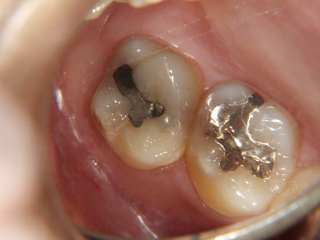

色 ・・・ 黒っぽく光沢がない、さびていることが多い

部位 ・・・ 奥歯の側面や咬み合わせ面、前歯の裏側(←こんなの見えるわけがない!)

範囲 ・・・ 小さいなかたまり状、他の金属修復物と比べて直線的ではない。

実際の写真で見てみましょう。

⇧ これは、どちらもアマルガムです。丸っこくちょこんと詰められています。